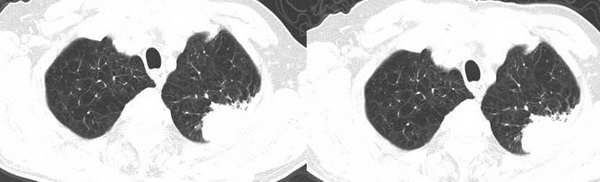

今年二月份ct检查

今天复查ct

左肺上叶尖后段胸膜下软组织密度结节,形态不规则,可见浅分叶,短毛刺,与胸膜广基相连,夹角成锐角。复查10个月后明显增大。考虑周围型肺癌。

和2月份片比较病灶明显增大,且有向胸壁侵犯的倾向,应该首先考虑周围型肺癌。

左肺尖后段胸膜下软组织密度肿块,形态不规则,有分叶,局部胸膜增厚,病灶周围见点片状影,与二月份片比较,肿块增大,考虑周围型肺癌伴阻塞性炎症,穿刺活检要有困难,因后方是肩胛骨躲不开.

感谢各位战友,现在病理出来了是左上肺腺癌